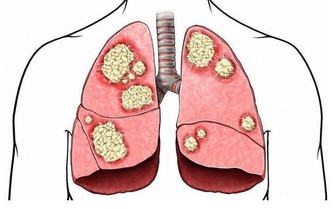

只見小於滿身滿臉的紅斑,上面有丘疹一樣的凸起,不少皮膚薄而脆弱,呈魚鱗狀,多處皸裂,皮損處甚至出漿出血。

看樣子還是典型的濕疹,但是大多數人長濕疹可能只是局部長一些,小於則是全身幾乎沒一塊好皮肉,為什麼會這麼嚴重?

其實,我們日常所說的濕疹,指的是皮膚由於內外因素產生炎症,常伴有劇烈瘙癢等反應的一種病症,就像咳嗽、流鼻水一樣,只是一種疾病的症狀,而非疾病本身。

關於濕疹的起因,目前醫學界還沒有確切定論,只能確定相當一部分的濕疹,是由於過敏、自身免疫力紊亂導致。